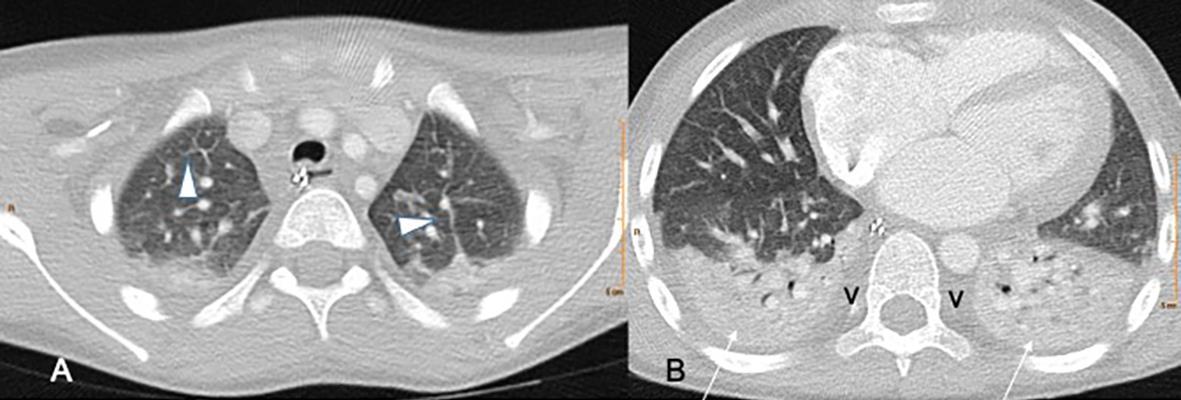

ADENOVIRUS

Bronchiolar and alveolar damage

MIS-C Embolism

Imaging of Covid 19 infection in children

MIS-C: Heart failure

60 Embolus Imaging of Covid 19 infection in children

MIS-C

61